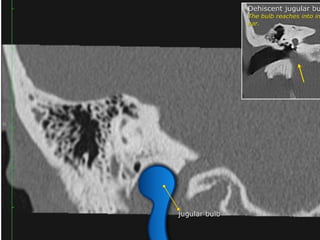

CT Temporal Bone Search Pattern with selected images :

•Jugular bulb